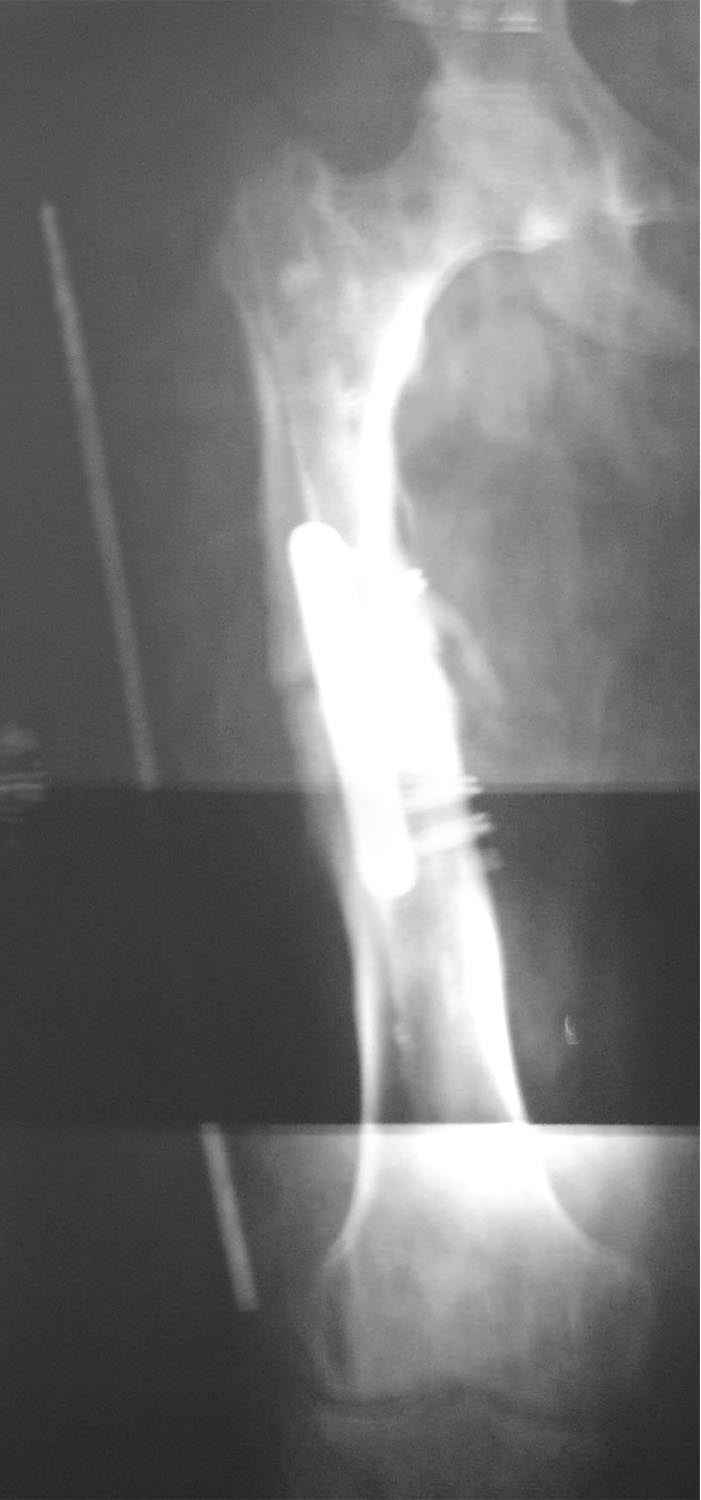

AC>По длине - уже "семь раз отмерили"? С длиной ве-таки как дело обстоит? И виден небольшой варус, надо бы и его устранить.

укорочение 15мм, клинически варуса нет. в приложении снимок на 2 пленках с центр на суставах, с приклеенной на уровне кости стержнем L-300mm,d-5mm.